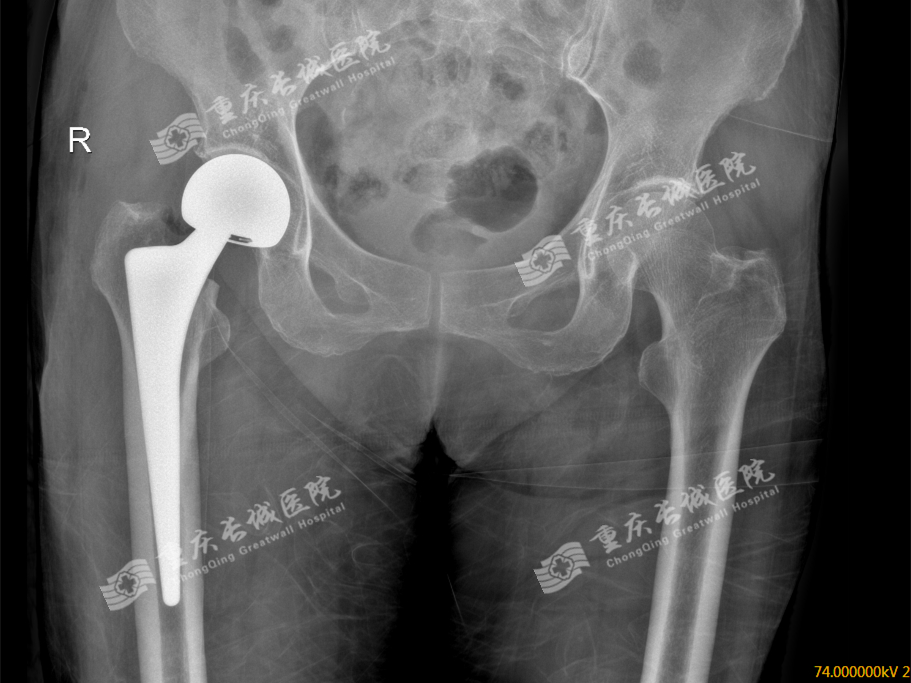

人工股骨头置换创伤小、手术时间短、出血少、麻醉风险小,临床实用价值大。对于高龄、骨折前活动能力低、合并有多种疾病、全身情况较差的患者选择人工股骨头置换为佳。而双极人工股骨头在单极人工股骨头的基础上增加了一个摩擦界面,可提供更好的功能和活动范围,有利于减少髋臼关节面磨损,使术后疼痛、假体松动及下沉率减少。对身体条件较差的患者采用双极人工股骨头置换。随访中部分患者患髋有时会酸痛,但不影响关节活动,能满足老年人日常生活需要。全髋关节置换随着手术技术的提高,手术时间明显缩短,创伤减轻,且麻醉技术能及时处理手术并发症,手术风险明显降低。

经过髋关节置换的治疗,我们再来看李嬢嬢的时候,她已经又能走能跑啦,我们的九龙坡坝坝舞一枝花又回来啦!